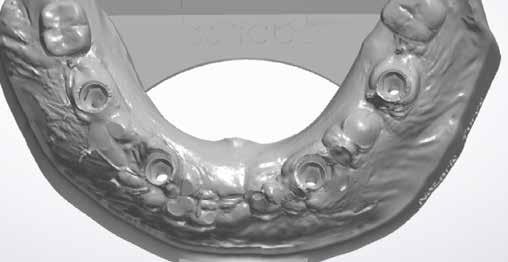

2. kép: A műtét előtti állapot – rágófelszíni nézet.

5. kép: A műtét előtti állapot felvétele – rágófelszíni nézet.

3shape TRIOS segítségével vett digitális intraorális lenyomat a teljes állcsontról. Virtuális fogeltávolítások, és BioHorizons implantátumok tervezése 3shape Implant Studio szoftverrel, BioHorizons implantátum könyvtárral (5-6. kép).